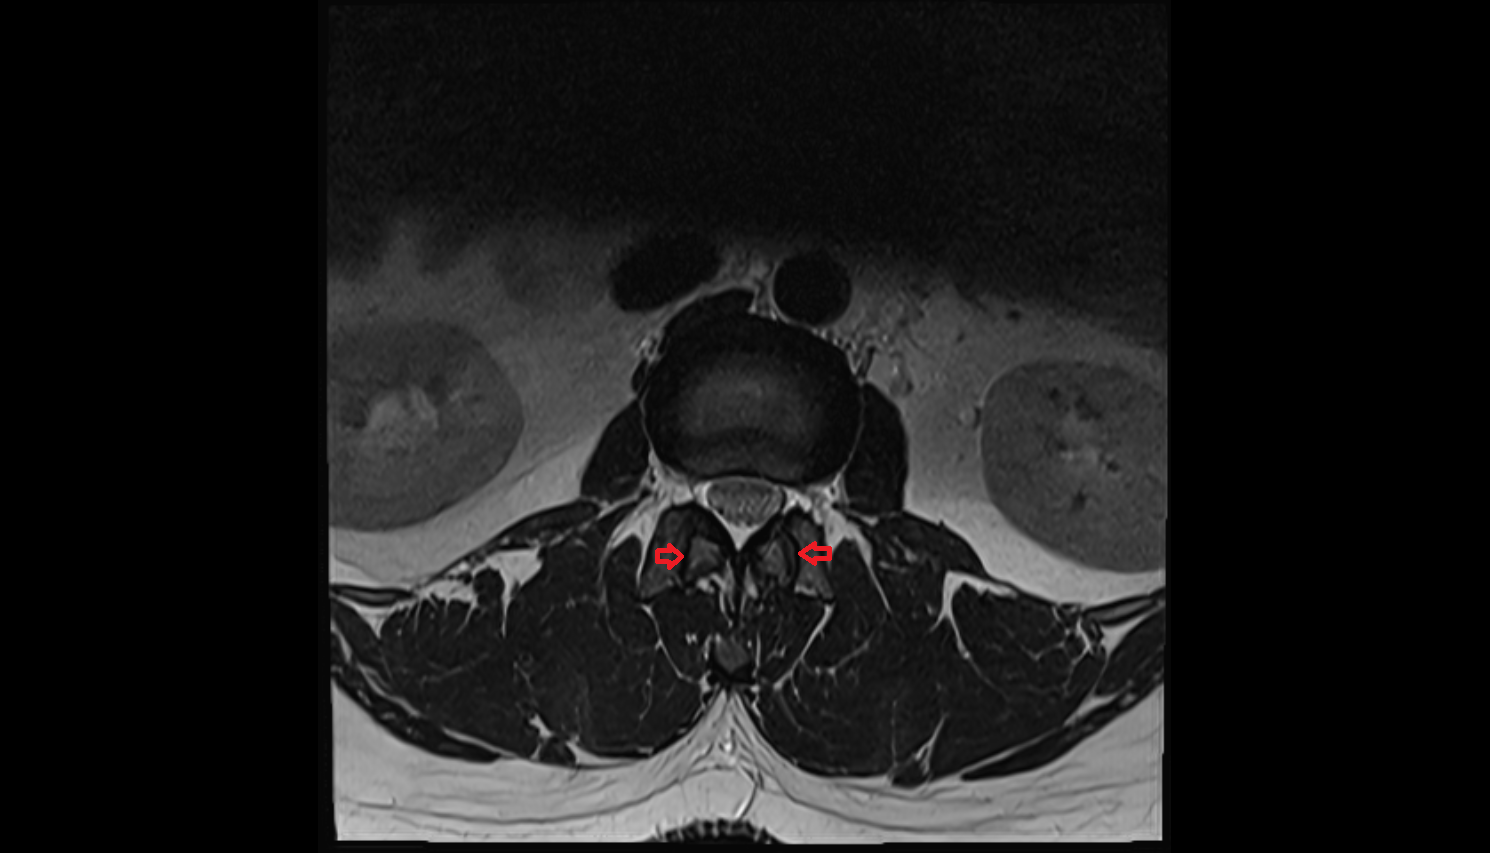

- Exit foramina